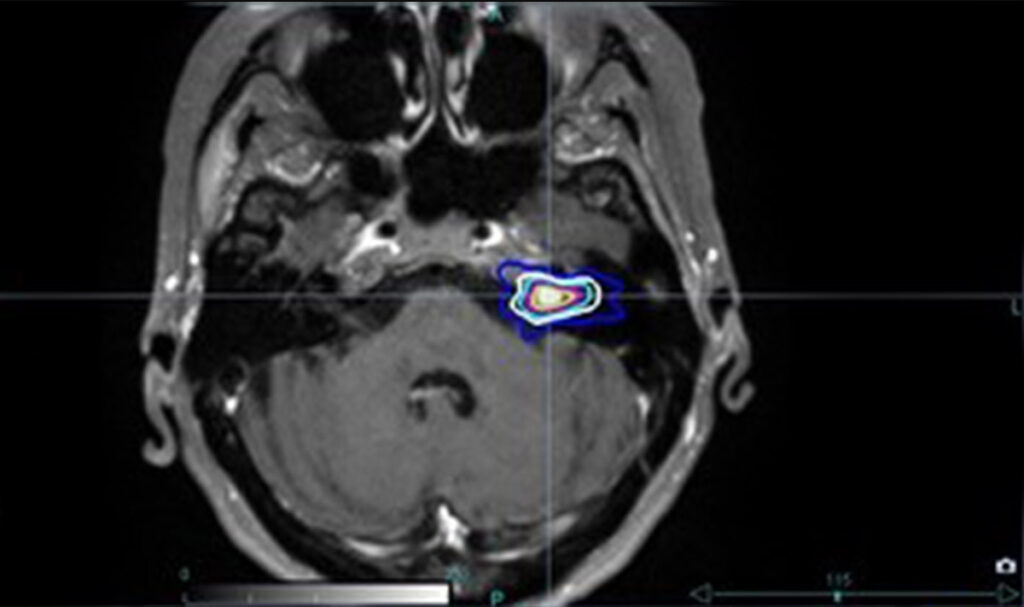

Das Akustikusneurinom.